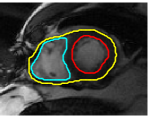

V-C LV and RV Segmentation: Quantitative Comparison to Commercial Software

We show experiments demonstrating the main use of our algorithm: in improving the prediction step of interactive segmentation methods. We show that less interaction is needed with our approach than a recent and widely used commercial cardiac segmentation software, Segment from Medviso [15, 44]. We perform quantitative assessment of the tracking performance of our method and compare it to Medviso. The evaluation was carried out on publicly available data sets, the MICCAI Left Ventricle Dataset [37] and the MICCAI Right Ventricle Dataset [25]. The validation dataset from [37] consists of 15 sets of cardiac cine-MRI images. Each set contains 6 to 20 2D slices from a 3D image, with each slice having 20 images of the cardiac phases. Similarly, the data set [25] contains 16 sets of cardiac cine-MRI images, each containing about 10 slices of 20 phases each. These data sets contain ground truth segmentations for left and right ventricles respectively (unfortunately ground truth for both the LV and RV is not available on a single dataset that we are aware of). Both methods start with the same initially correct segmentation, and subsequent frames are segmented via propagation. No manual interaction is used as we wish to show that our method would require less interaction. The regularity parameter in our method is found by choosing so that the results are closest to ground truth in a few training cases. The same parameter is then used for all other cases.

Figures 8 and 9 shows some sample tracking results of the proposed method and Medviso on full cardiac cycles of two different cases on both the LV dataset and the RV dataset. The ground truth (yellow) is superimposed when available. A summary of the results on the entire datasets is shown in Table I. The accuracy with respect to ground truth is measured using average perpendicular distance (APD) and dice metric (DM) for left ventricle, and Hausdorff distance (HD) and DM for the right ventricle. These metrics are chosen since they are the standard ones used on these datasets. Both qualitative and quantitative results show that our proposed method leads to more accurate segmentation of the ventricles and thus leads to less interaction than segmentation propagation schemes in than Medviso.